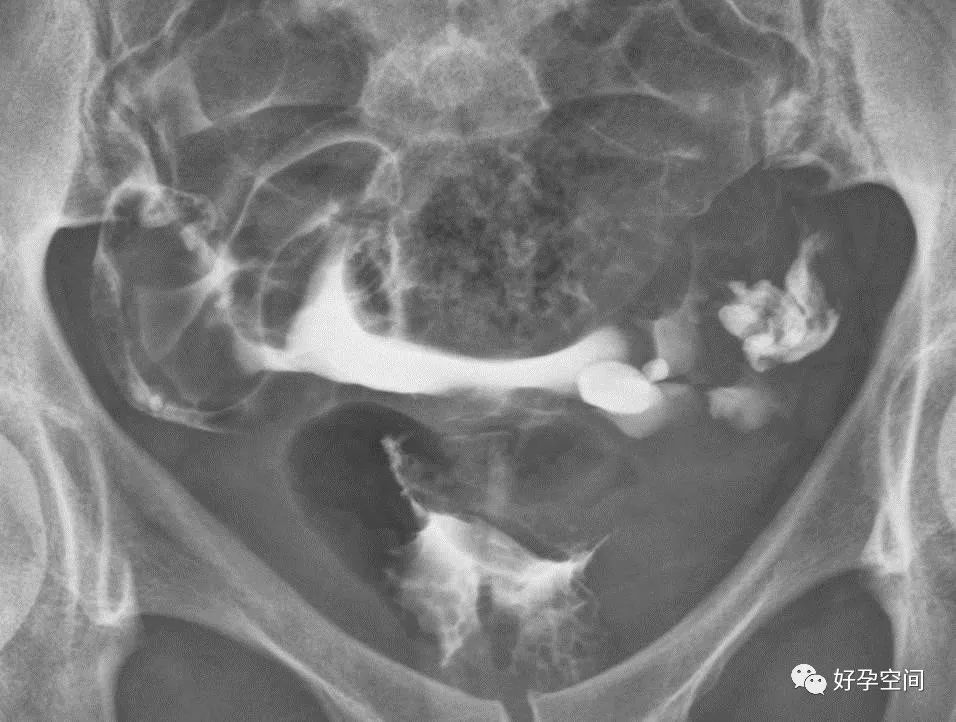

双侧输卵管水平走行